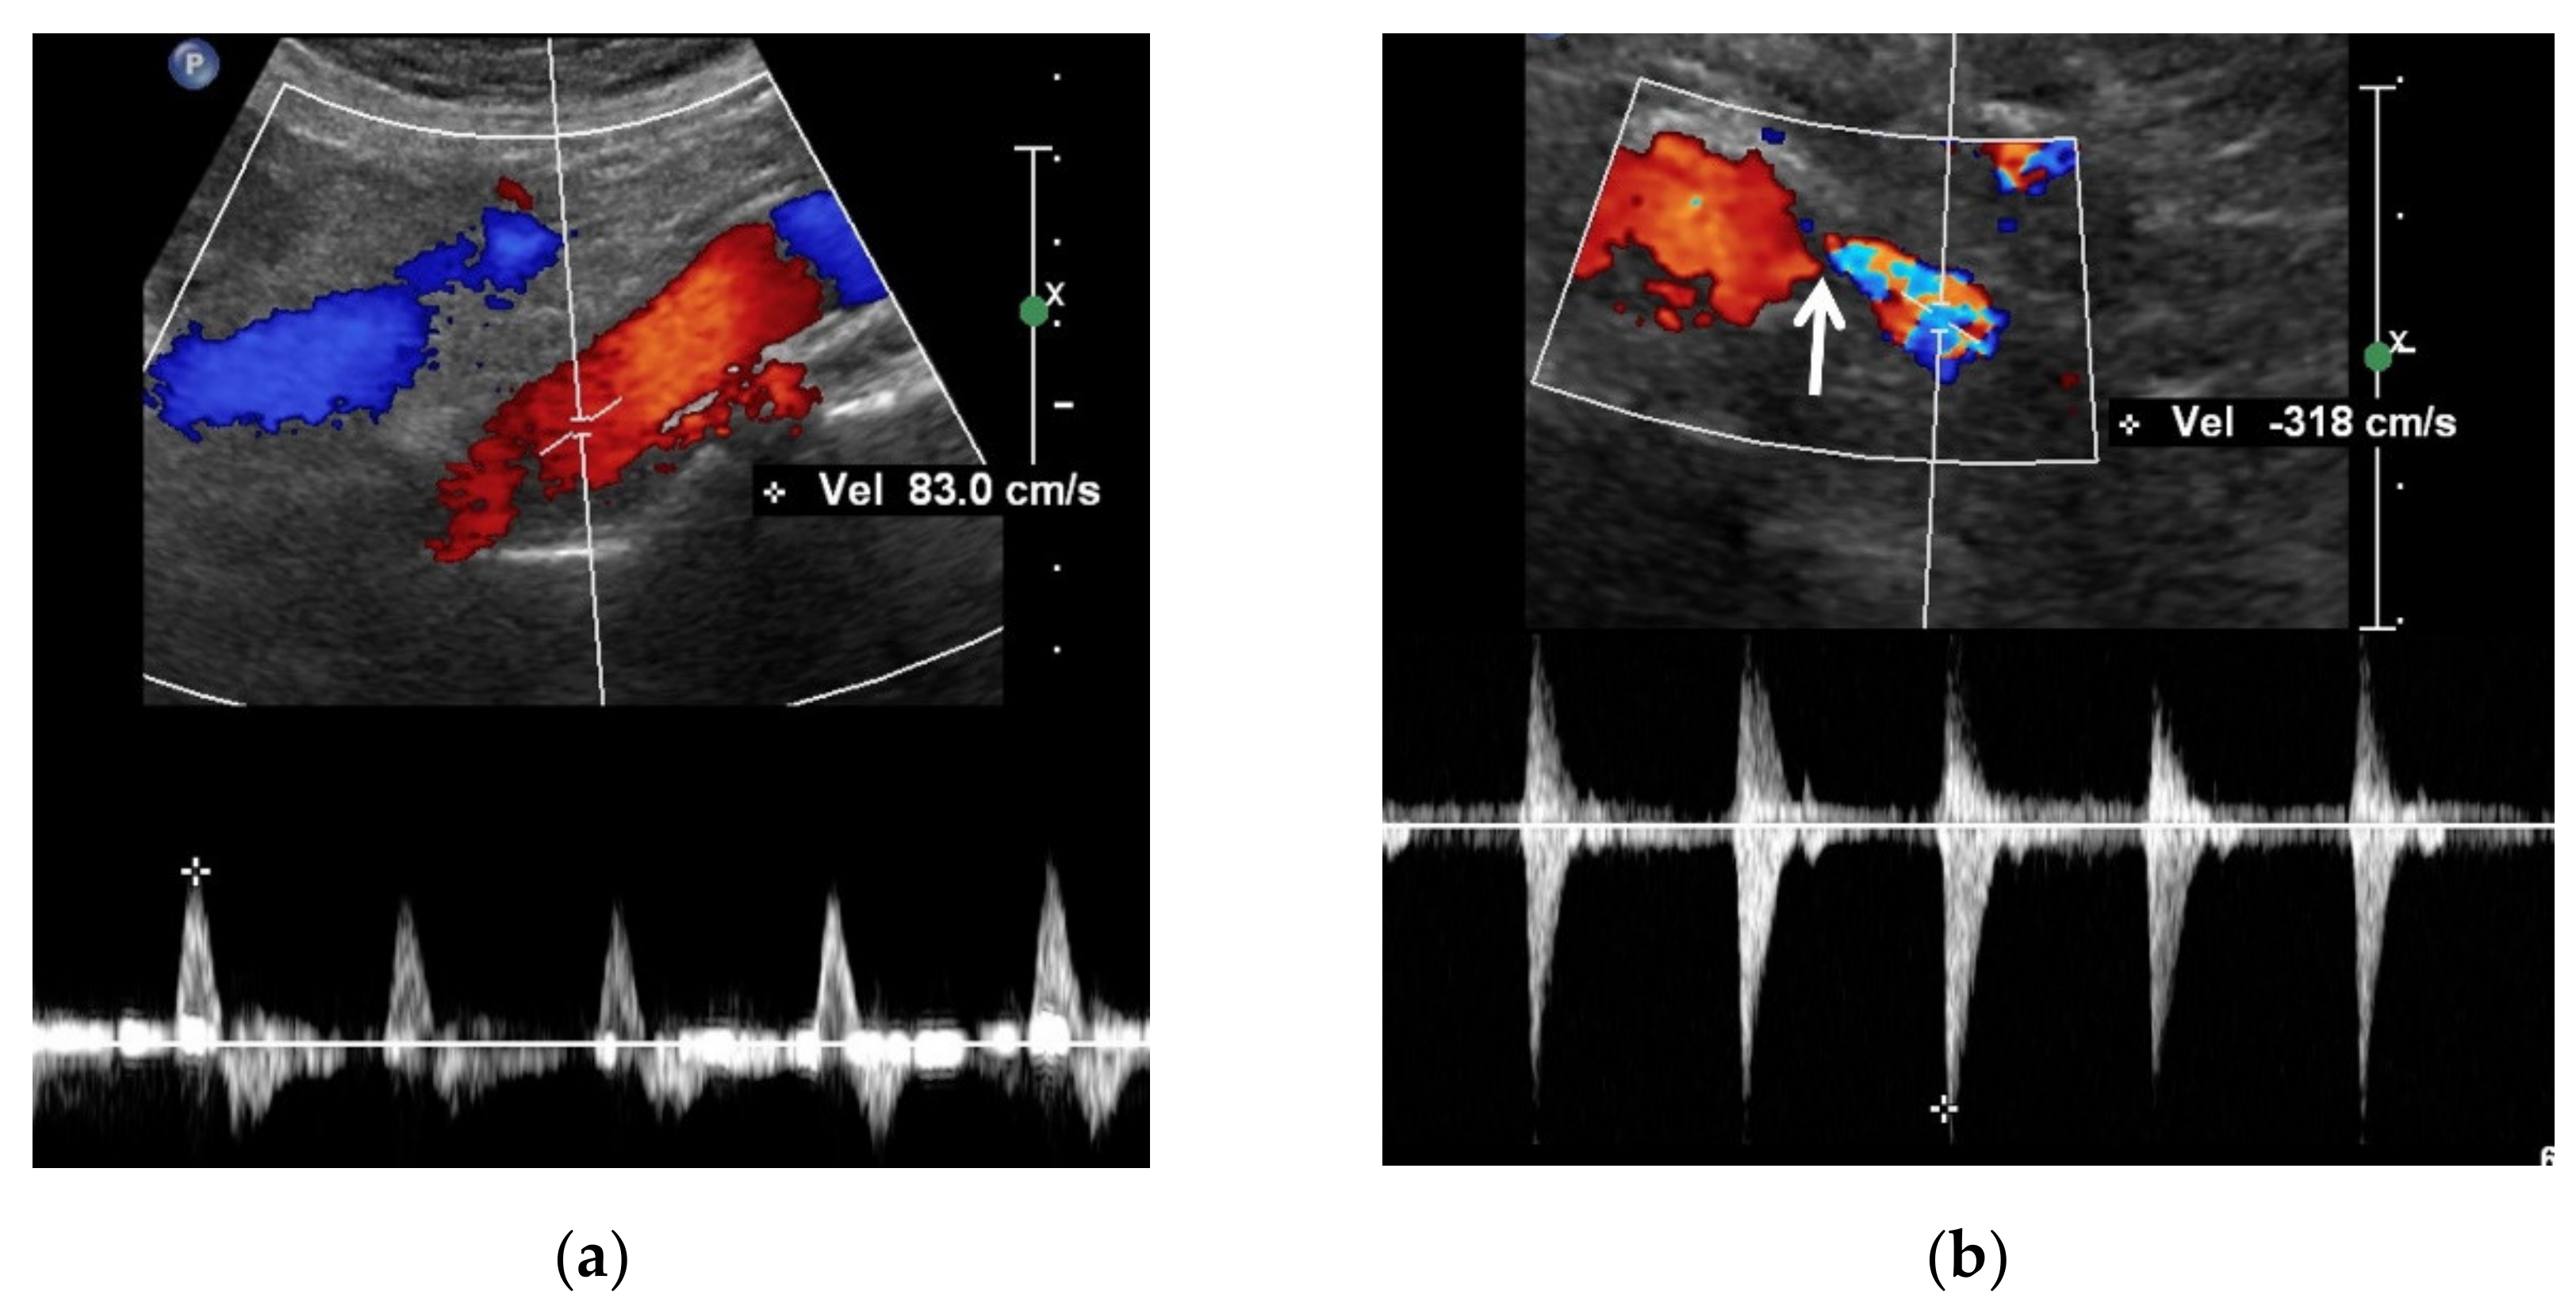

Contrast-enhanced US can be used to directly depict stenosis in the renal artery and poststenotic dilatation [23,66] (Figure 5). In addition, the US signal of an involved kidney is lower than that of the other kidney in the case of unilateral RAS [67]. The renal artery is continuously depicted when the mechanical index is low. Additionally, if a flash mode is selected during the contrast-enhanced US scan, renal artery imaging can be restarted because the in-plane US contrast material is almost all destroyed over a short period. Contrast-enhanced US can depict the renal artery only in the beginning. Renal veins and many adjacent vessels are immediately visualized following renal circulation, and, as such, may prevent precise assessment of RAS. This flash mode has the limitation where the US signal of the renal artery is weaker than that of the renal artery in the beginning of contrast-enhanced US.

Figure 5.

Contrast-enhanced US in a 60-year-old man. Contrast-enhanced US axial image (left side), which was obtained 20–30 s after Sonovue (Bracco, Milan, Italy) was intravenously injected, shows a focal stenosis in the proximal left renal artery. Gray-scale US axial image (right side), which corresponds to the contrast-enhanced US axial image, shows calcifications (white arrow) in the stenotic wall of the proximal left renal artery. LRV, left renal vein.